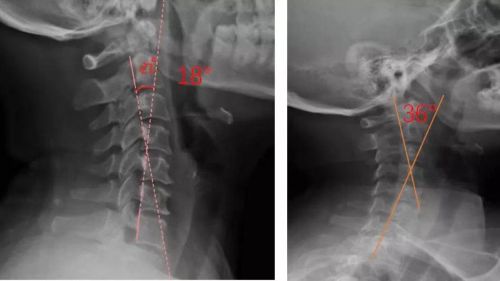

患者適配前后側位X光,佩戴前18°,適配后36°

對于頸椎病患者,合理設計的頸椎枕,能夠緊密適合頸椎,矯正頸椎生理曲度;再根據頸椎曲度改善情況,隨時間慢慢調整3D打印頸椎枕曲度,使變直的頸椎逐漸形成正常的生理曲度,改善頸肩痛的癥狀。